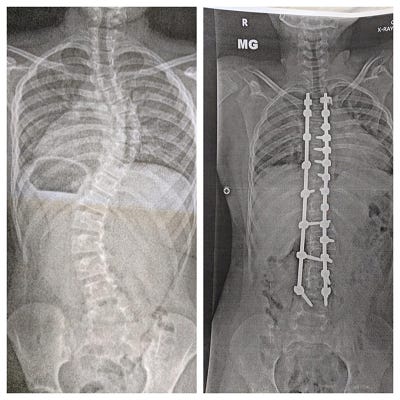

When I later looked back at that first column, I realized how dark and desperate much of it sounded. Doctors not returning phone calls; intense MRIs; my son having to wear an upper-body brace 23 hours a day for years to come (that might not even make a difference); the likelihood of major spine surgery to prevent my son’s spine-curvature from crushing his vital organs… It was a real downer.

I took her up on the offer, and my daughter and I drove a couple miles to the hospital to get her x-rayed. Within a couple hours, the results popped up in our medical portal and my heart sank when I saw the image. She definitely had C-curve scoliosis, and though it didn’t look nearly as bad as my son’s did years earlier, it wasn’t exactly mild either.

Studying my daughter’s x-ray, he measured her curve to be about 22 degrees. As a specialist dealing with extreme cases, it was probably on the low end of what he’s used to seeing, and about half of what my son’s initial curvature had been. That, along with my daughter being four years older than my son had been, and nearing the end of her vertical growth capacity (something that’s much easier to determine in girls than in boys), he was optimistic that no treatment would be needed.